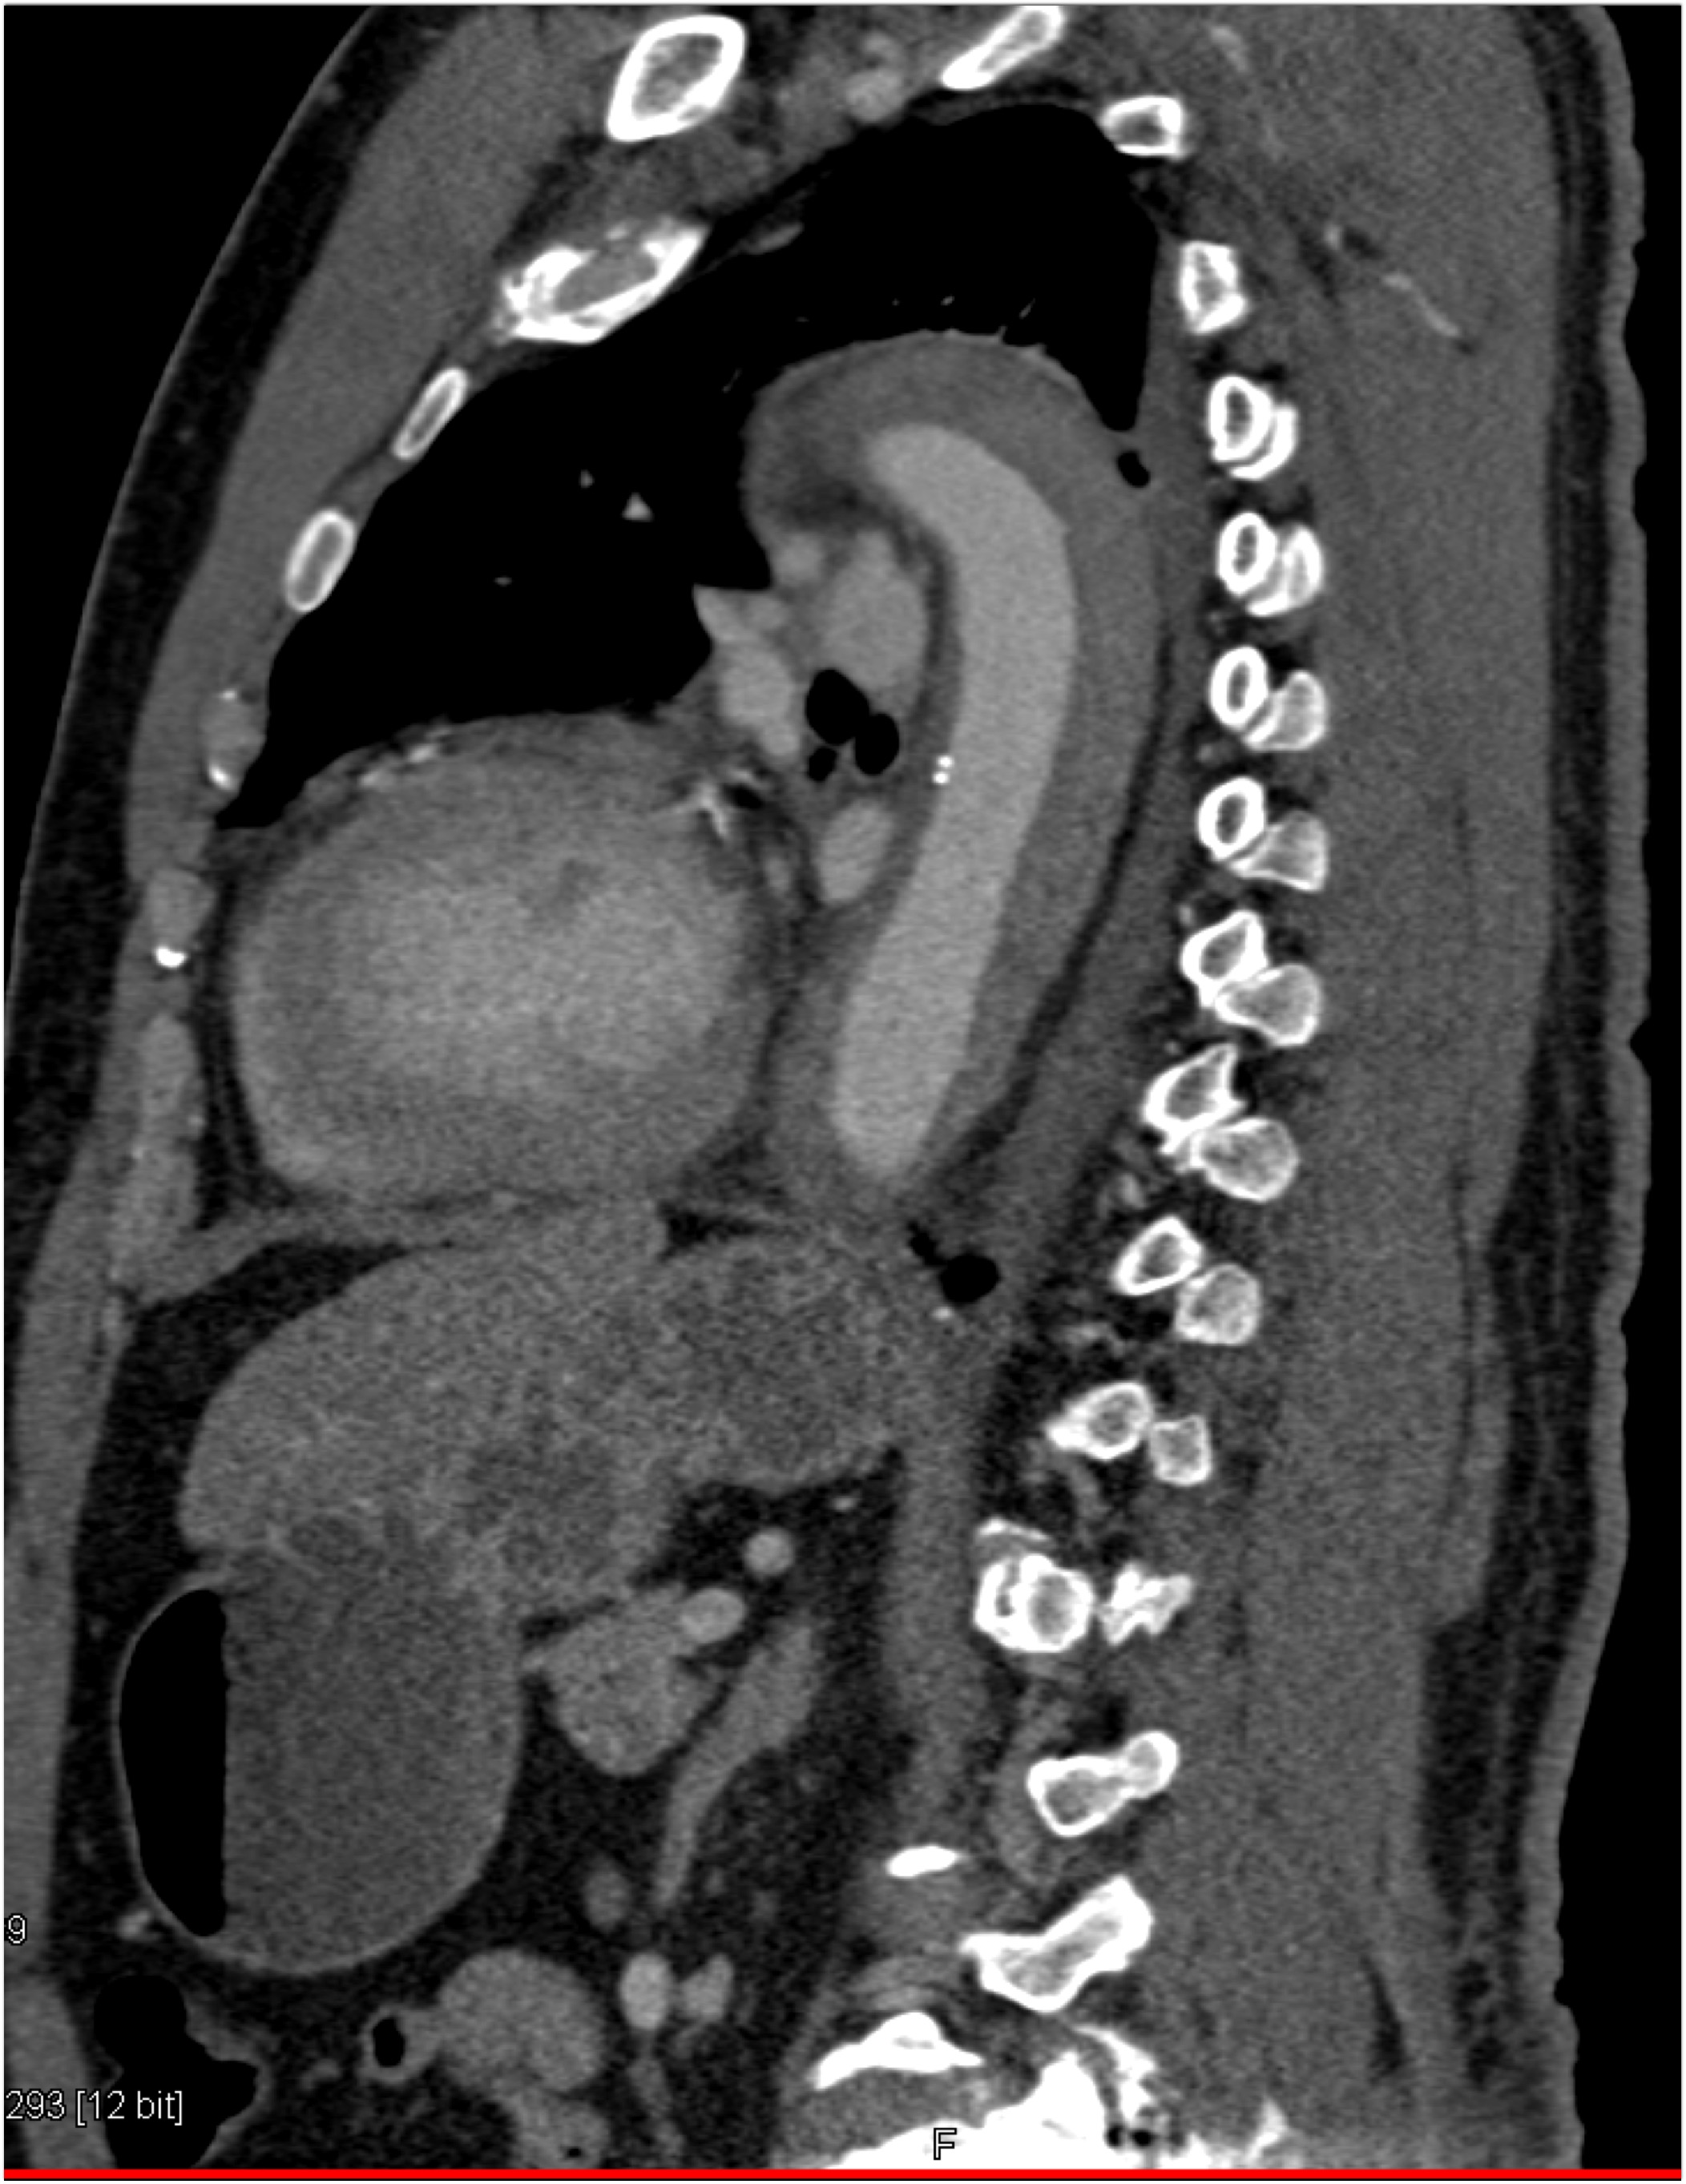

4) The most likely diagnosis in this patient with acute chest pain is?

type A dissection

intramural hematoma

type B dissection

Takayasu’s aortitis